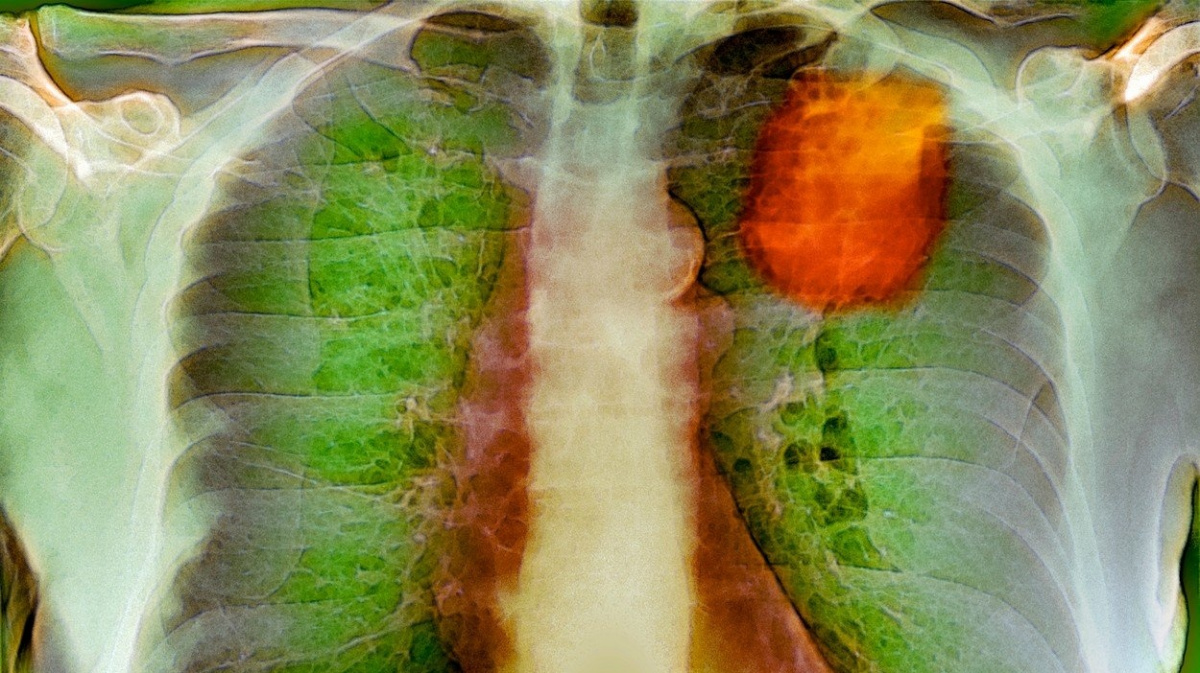

Rakovina pliczdroj: Profimedia

S nejnovějším příkladem o průniku umělé inteligence do zdravotnictví přišla studie publikována v časopisu Nature, která vychází z dílny AI výzkumníků společnosti Google. Ti naučili nový algoritmus strojového učení detekovat ze snímků získaných tomografem potenciální přítomnost nádoru s úspěšností na 94,4 procenta. To je na úrovni přesnosti srovnatelné s lékařskými pracovníky - v některých ohledech algoritmus dokonce lidi předčil.

Strojový systém tuto přesnost prokázal v analýze 6716 případů rakoviny plic z amerického registru rakoviny plic, údaje navíc s podobnou přesností podpořila i detekce 1139 nezávislých klinických případů. Studie tedy stojí na dvou separátních pracích - jedné, kdy byly byly známy výsledky (stroj řešil starší případy), a jedné, kdy nikoliv. V první případě si AI vedla lépe než lidé, v druhém byla na stejné úrovni přesnosti.